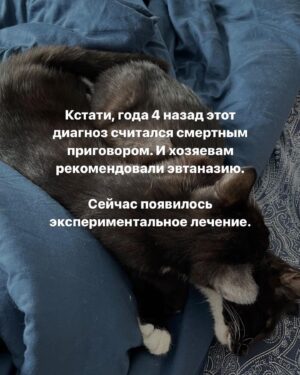

Caption : Про наших «блох», их болезнь и про классы от нас с @baturo_ Друзья, мы в конце января с Андреем взяли 3х котят из приюта. Прелестные, ласковые создания. К сожалению, двое из них заболели FIP (об этом рассказывала неделю назад, можно прочесть в карусели или в актуальном) Мы с Андреем уже очень сильно их любим, сдаваться не намерены. Четко и уверенно настроены на лучшее. Поэтому мы организовываем классы в Санкт-Петербурге 22 апреля‼️, все средства от которых пойдут на лечение наших блох, Нео и Абу. ⚫️22 апреля 15.00-17.00- Андрей Батуро (изоляция, виды) 17.00-19.00- Баина (партерная техника, основы безопасности в партере, грамотное распределение веса) ⚫️Стоимость: 1 класс-1500 руб 2 класса-2500 руб Место проведения: Jonathan, измайловский проспект, 2, зал 14 (вход со стороны измайловского проспекта) Код от домофона Внизу #1962 Наверху 2703# Проведите время с пользой для себя и помогите поправить здоровье двум маленьким котятам) Для записи пишите в директ) Мы очень будем рады видеть всех, а также просим максимально помочь с распространением этого поста, чтобы больше человек могли увидеть его)) P.S пользуясь случаем, хочу поблагодарить всех неравнодушных, кто просто захотел помочь монеткой🙏🏻🙏🏻 Это до слез ценно!Likes : 1330

Caption : Про наших «блох», их болезнь и про классы от нас с @baturo_ Друзья, мы в конце января с Андреем взяли 3х котят из приюта. Прелестные, ласковые создания. К сожалению, двое из них заболели FIP (об этом рассказывала неделю назад, можно прочесть в карусели или в актуальном) Мы с Андреем уже очень сильно их любим, сдаваться не намерены. Четко и уверенно настроены на лучшее. Поэтому мы организовываем классы в Санкт-Петербурге 22 апреля‼️, все средства от которых пойдут на лечение наших блох, Нео и Абу. ⚫️22 апреля 15.00-17.00- Андрей Батуро (изоляция, виды) 17.00-19.00- Баина (партерная техника, основы безопасности в партере, грамотное распределение веса) ⚫️Стоимость: 1 класс-1500 руб 2 класса-2500 руб Место проведения: Jonathan, измайловский проспект, 2, зал 14 (вход со стороны измайловского проспекта) Код от домофона Внизу #1962 Наверху 2703# Проведите время с пользой для себя и помогите поправить здоровье двум маленьким котятам) Для записи пишите в директ) Мы очень будем рады видеть всех, а также просим максимально помочь с распространением этого поста, чтобы больше человек могли увидеть его)) P.S пользуясь случаем, хочу поблагодарить всех неравнодушных, кто просто захотел помочь монеткой🙏🏻🙏🏻 Это до слез ценно!Likes : 1330

Caption : Про наших «блох», их болезнь и про классы от нас с @baturo_ Друзья, мы в конце января с Андреем взяли 3х котят из приюта. Прелестные, ласковые создания. К сожалению, двое из них заболели FIP (об этом рассказывала неделю назад, можно прочесть в карусели или в актуальном) Мы с Андреем уже очень сильно их любим, сдаваться не намерены. Четко и уверенно настроены на лучшее. Поэтому мы организовываем классы в Санкт-Петербурге 22 апреля‼️, все средства от которых пойдут на лечение наших блох, Нео и Абу. ⚫️22 апреля 15.00-17.00- Андрей Батуро (изоляция, виды) 17.00-19.00- Баина (партерная техника, основы безопасности в партере, грамотное распределение веса) ⚫️Стоимость: 1 класс-1500 руб 2 класса-2500 руб Место проведения: Jonathan, измайловский проспект, 2, зал 14 (вход со стороны измайловского проспекта) Код от домофона Внизу #1962 Наверху 2703# Проведите время с пользой для себя и помогите поправить здоровье двум маленьким котятам) Для записи пишите в директ) Мы очень будем рады видеть всех, а также просим максимально помочь с распространением этого поста, чтобы больше человек могли увидеть его)) P.S пользуясь случаем, хочу поблагодарить всех неравнодушных, кто просто захотел помочь монеткой🙏🏻🙏🏻 Это до слез ценно!Likes : 1330

Caption : Про наших «блох», их болезнь и про классы от нас с @baturo_ Друзья, мы в конце января с Андреем взяли 3х котят из приюта. Прелестные, ласковые создания. К сожалению, двое из них заболели FIP (об этом рассказывала неделю назад, можно прочесть в карусели или в актуальном) Мы с Андреем уже очень сильно их любим, сдаваться не намерены. Четко и уверенно настроены на лучшее. Поэтому мы организовываем классы в Санкт-Петербурге 22 апреля‼️, все средства от которых пойдут на лечение наших блох, Нео и Абу. ⚫️22 апреля 15.00-17.00- Андрей Батуро (изоляция, виды) 17.00-19.00- Баина (партерная техника, основы безопасности в партере, грамотное распределение веса) ⚫️Стоимость: 1 класс-1500 руб 2 класса-2500 руб Место проведения: Jonathan, измайловский проспект, 2, зал 14 (вход со стороны измайловского проспекта) Код от домофона Внизу #1962 Наверху 2703# Проведите время с пользой для себя и помогите поправить здоровье двум маленьким котятам) Для записи пишите в директ) Мы очень будем рады видеть всех, а также просим максимально помочь с распространением этого поста, чтобы больше человек могли увидеть его)) P.S пользуясь случаем, хочу поблагодарить всех неравнодушных, кто просто захотел помочь монеткой🙏🏻🙏🏻 Это до слез ценно!Likes : 1330

Caption : Про наших «блох», их болезнь и про классы от нас с @baturo_ Друзья, мы в конце января с Андреем взяли 3х котят из приюта. Прелестные, ласковые создания. К сожалению, двое из них заболели FIP (об этом рассказывала неделю назад, можно прочесть в карусели или в актуальном) Мы с Андреем уже очень сильно их любим, сдаваться не намерены. Четко и уверенно настроены на лучшее. Поэтому мы организовываем классы в Санкт-Петербурге 22 апреля‼️, все средства от которых пойдут на лечение наших блох, Нео и Абу. ⚫️22 апреля 15.00-17.00- Андрей Батуро (изоляция, виды) 17.00-19.00- Баина (партерная техника, основы безопасности в партере, грамотное распределение веса) ⚫️Стоимость: 1 класс-1500 руб 2 класса-2500 руб Место проведения: Jonathan, измайловский проспект, 2, зал 14 (вход со стороны измайловского проспекта) Код от домофона Внизу #1962 Наверху 2703# Проведите время с пользой для себя и помогите поправить здоровье двум маленьким котятам) Для записи пишите в директ) Мы очень будем рады видеть всех, а также просим максимально помочь с распространением этого поста, чтобы больше человек могли увидеть его)) P.S пользуясь случаем, хочу поблагодарить всех неравнодушных, кто просто захотел помочь монеткой🙏🏻🙏🏻 Это до слез ценно!Likes : 1330

Caption : Про наших «блох», их болезнь и про классы от нас с @baturo_ Друзья, мы в конце января с Андреем взяли 3х котят из приюта. Прелестные, ласковые создания. К сожалению, двое из них заболели FIP (об этом рассказывала неделю назад, можно прочесть в карусели или в актуальном) Мы с Андреем уже очень сильно их любим, сдаваться не намерены. Четко и уверенно настроены на лучшее. Поэтому мы организовываем классы в Санкт-Петербурге 22 апреля‼️, все средства от которых пойдут на лечение наших блох, Нео и Абу. ⚫️22 апреля 15.00-17.00- Андрей Батуро (изоляция, виды) 17.00-19.00- Баина (партерная техника, основы безопасности в партере, грамотное распределение веса) ⚫️Стоимость: 1 класс-1500 руб 2 класса-2500 руб Место проведения: Jonathan, измайловский проспект, 2, зал 14 (вход со стороны измайловского проспекта) Код от домофона Внизу #1962 Наверху 2703# Проведите время с пользой для себя и помогите поправить здоровье двум маленьким котятам) Для записи пишите в директ) Мы очень будем рады видеть всех, а также просим максимально помочь с распространением этого поста, чтобы больше человек могли увидеть его)) P.S пользуясь случаем, хочу поблагодарить всех неравнодушных, кто просто захотел помочь монеткой🙏🏻🙏🏻 Это до слез ценно!Likes : 1330

Caption : Про наших «блох», их болезнь и про классы от нас с @baturo_ Друзья, мы в конце января с Андреем взяли 3х котят из приюта. Прелестные, ласковые создания. К сожалению, двое из них заболели FIP (об этом рассказывала неделю назад, можно прочесть в карусели или в актуальном) Мы с Андреем уже очень сильно их любим, сдаваться не намерены. Четко и уверенно настроены на лучшее. Поэтому мы организовываем классы в Санкт-Петербурге 22 апреля‼️, все средства от которых пойдут на лечение наших блох, Нео и Абу. ⚫️22 апреля 15.00-17.00- Андрей Батуро (изоляция, виды) 17.00-19.00- Баина (партерная техника, основы безопасности в партере, грамотное распределение веса) ⚫️Стоимость: 1 класс-1500 руб 2 класса-2500 руб Место проведения: Jonathan, измайловский проспект, 2, зал 14 (вход со стороны измайловского проспекта) Код от домофона Внизу #1962 Наверху 2703# Проведите время с пользой для себя и помогите поправить здоровье двум маленьким котятам) Для записи пишите в директ) Мы очень будем рады видеть всех, а также просим максимально помочь с распространением этого поста, чтобы больше человек могли увидеть его)) P.S пользуясь случаем, хочу поблагодарить всех неравнодушных, кто просто захотел помочь монеткой🙏🏻🙏🏻 Это до слез ценно!Likes : 1330

Caption : Про наших «блох», их болезнь и про классы от нас с @baturo_ Друзья, мы в конце января с Андреем взяли 3х котят из приюта. Прелестные, ласковые создания. К сожалению, двое из них заболели FIP (об этом рассказывала неделю назад, можно прочесть в карусели или в актуальном) Мы с Андреем уже очень сильно их любим, сдаваться не намерены. Четко и уверенно настроены на лучшее. Поэтому мы организовываем классы в Санкт-Петербурге 22 апреля‼️, все средства от которых пойдут на лечение наших блох, Нео и Абу. ⚫️22 апреля 15.00-17.00- Андрей Батуро (изоляция, виды) 17.00-19.00- Баина (партерная техника, основы безопасности в партере, грамотное распределение веса) ⚫️Стоимость: 1 класс-1500 руб 2 класса-2500 руб Место проведения: Jonathan, измайловский проспект, 2, зал 14 (вход со стороны измайловского проспекта) Код от домофона Внизу #1962 Наверху 2703# Проведите время с пользой для себя и помогите поправить здоровье двум маленьким котятам) Для записи пишите в директ) Мы очень будем рады видеть всех, а также просим максимально помочь с распространением этого поста, чтобы больше человек могли увидеть его)) P.S пользуясь случаем, хочу поблагодарить всех неравнодушных, кто просто захотел помочь монеткой🙏🏻🙏🏻 Это до слез ценно!Likes : 1330

Caption : Про наших «блох», их болезнь и про классы от нас с @baturo_ Друзья, мы в конце января с Андреем взяли 3х котят из приюта. Прелестные, ласковые создания. К сожалению, двое из них заболели FIP (об этом рассказывала неделю назад, можно прочесть в карусели или в актуальном) Мы с Андреем уже очень сильно их любим, сдаваться не намерены. Четко и уверенно настроены на лучшее. Поэтому мы организовываем классы в Санкт-Петербурге 22 апреля‼️, все средства от которых пойдут на лечение наших блох, Нео и Абу. ⚫️22 апреля 15.00-17.00- Андрей Батуро (изоляция, виды) 17.00-19.00- Баина (партерная техника, основы безопасности в партере, грамотное распределение веса) ⚫️Стоимость: 1 класс-1500 руб 2 класса-2500 руб Место проведения: Jonathan, измайловский проспект, 2, зал 14 (вход со стороны измайловского проспекта) Код от домофона Внизу #1962 Наверху 2703# Проведите время с пользой для себя и помогите поправить здоровье двум маленьким котятам) Для записи пишите в директ) Мы очень будем рады видеть всех, а также просим максимально помочь с распространением этого поста, чтобы больше человек могли увидеть его)) P.S пользуясь случаем, хочу поблагодарить всех неравнодушных, кто просто захотел помочь монеткой🙏🏻🙏🏻 Это до слез ценно!Likes : 1330

Caption : Про наших «блох», их болезнь и про классы от нас с @baturo_ Друзья, мы в конце января с Андреем взяли 3х котят из приюта. Прелестные, ласковые создания. К сожалению, двое из них заболели FIP (об этом рассказывала неделю назад, можно прочесть в карусели или в актуальном) Мы с Андреем уже очень сильно их любим, сдаваться не намерены. Четко и уверенно настроены на лучшее. Поэтому мы организовываем классы в Санкт-Петербурге 22 апреля‼️, все средства от которых пойдут на лечение наших блох, Нео и Абу. ⚫️22 апреля 15.00-17.00- Андрей Батуро (изоляция, виды) 17.00-19.00- Баина (партерная техника, основы безопасности в партере, грамотное распределение веса) ⚫️Стоимость: 1 класс-1500 руб 2 класса-2500 руб Место проведения: Jonathan, измайловский проспект, 2, зал 14 (вход со стороны измайловского проспекта) Код от домофона Внизу #1962 Наверху 2703# Проведите время с пользой для себя и помогите поправить здоровье двум маленьким котятам) Для записи пишите в директ) Мы очень будем рады видеть всех, а также просим максимально помочь с распространением этого поста, чтобы больше человек могли увидеть его)) P.S пользуясь случаем, хочу поблагодарить всех неравнодушных, кто просто захотел помочь монеткой🙏🏻🙏🏻 Это до слез ценно!Likes : 1330